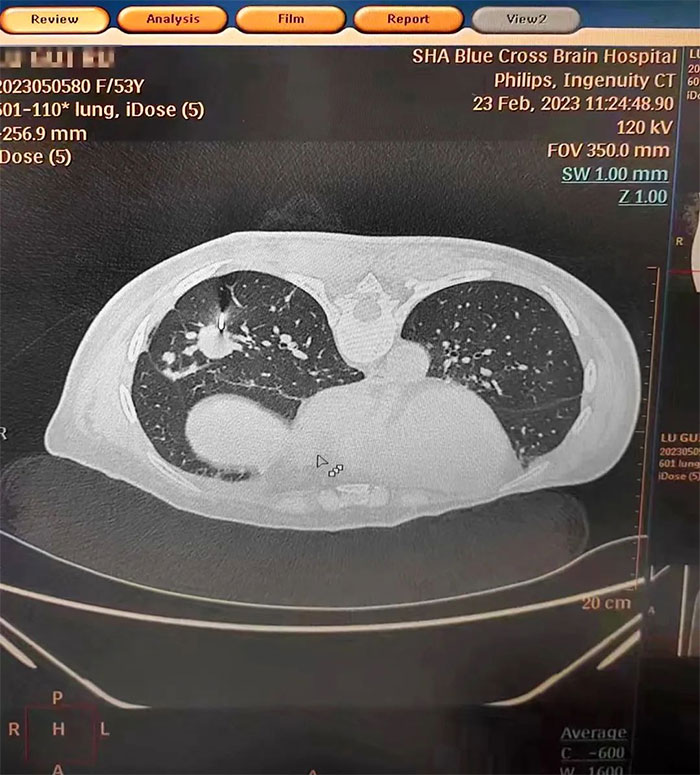

▲ 肺CT顯示,穿刺針穿刺到位

在明確告知風險并經家屬同意后,張澤明主任在CT引導下精準定位,選擇合適的進針位置,一次穿刺成功,順利取得組織樣本。手術過程順利,未出現(xiàn)明顯并發(fā)癥。經送檢,術后病理診斷為腺癌,結合臨床病史符合乳腺癌轉移,為制定下一步個體化綜合治療方案提供了重要依據(jù)。